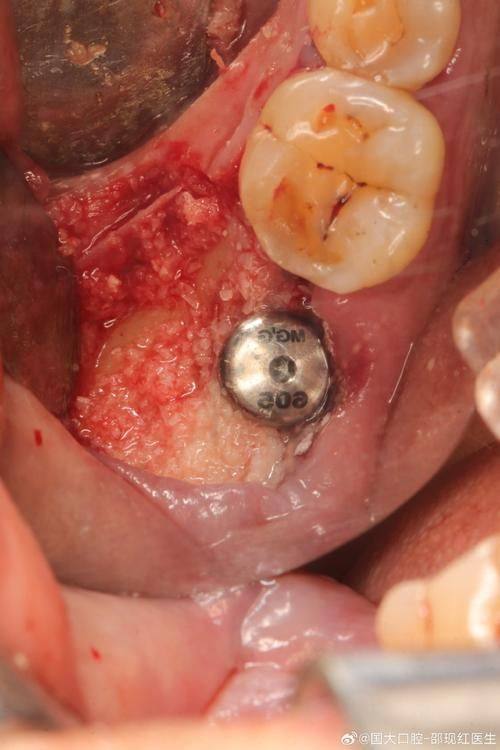

2. 微创种植:微创种植是一种精良的种植技术,它通过微小的切口将种植体植入牙槽骨内,减少了手术的创伤和疼痛,术后修复也更快。何医生熟练掌握这种技术,能够在确保种植成效的前提下,较大程度地减轻患者的痛苦。在手术过程中,她会运用精细的操作和精良的设备,确保种植过程顺利进行。

4. 数字化种植:数字化种植是利用计算机技术进行种植手术的规划和模拟。何医生紧跟时代潮流,熟练掌握数字化种植技术。通过数字化设备,可以严谨地获取患者口腔的三维信息,为种植手术提供更加正确的数据支持。在手术中,医生可以按照预先规划的方案进行精细操作,提高了手术的成功几率和安心性。